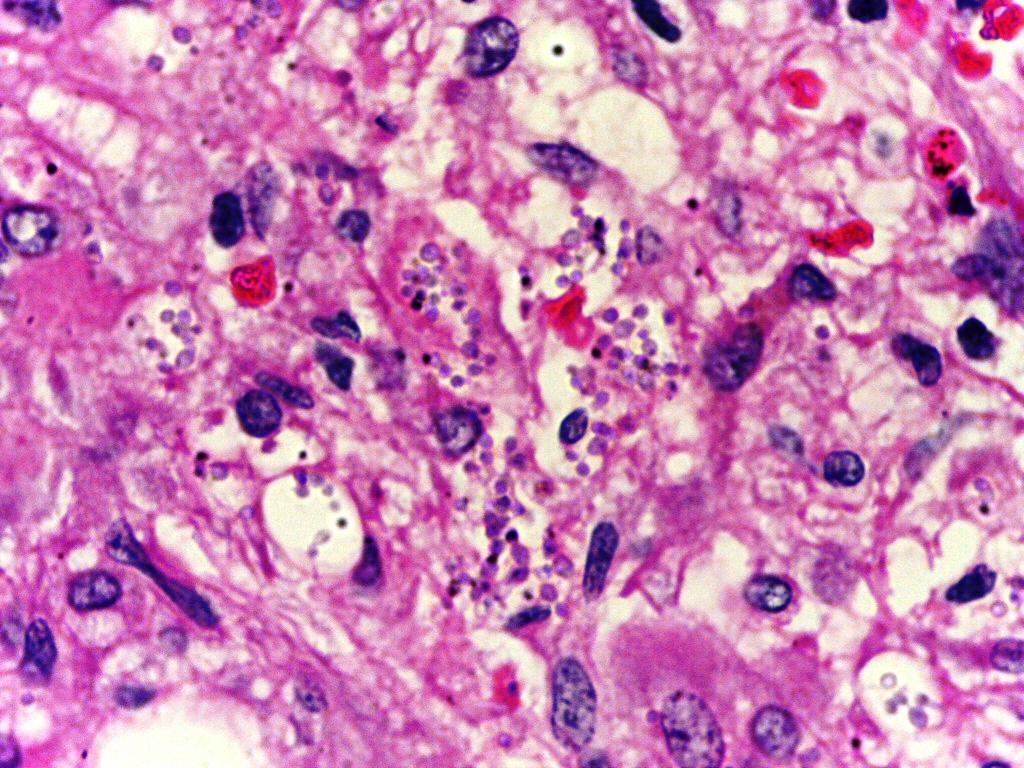

The researchers demonstrated that IL-4-producing B cells are not necessary in protection from leishmaniasis and their absence led to reduced susceptibility to the disease. The opposite was true for schistosomiasis as absence of these cells was detrimental to mouse health. The mice with B cells deficient in IL-4Rα had mRNA cytokine expression in acute infection that was consistent with Th1 dichotomy and had impaired Type 2 responses. The researchers showed that the IL-4-producing B cells were important in inducing Th2 responses.